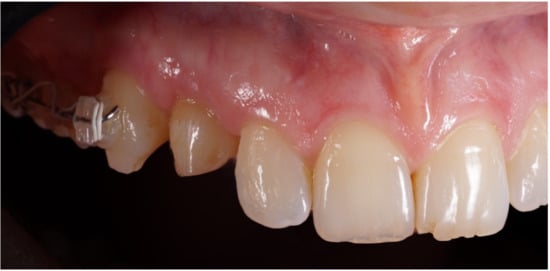

Figure 2.

Lateral preoperative view.